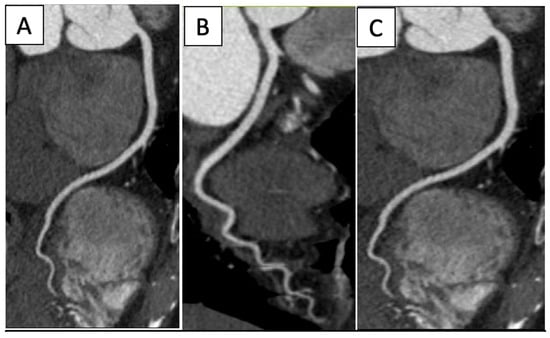

| Imaging Modality | Imaging Illustrations | Description |

|---|---|---|

| Cardiac CT | ![]() | Left-anterior descending artery on cardiac CT |